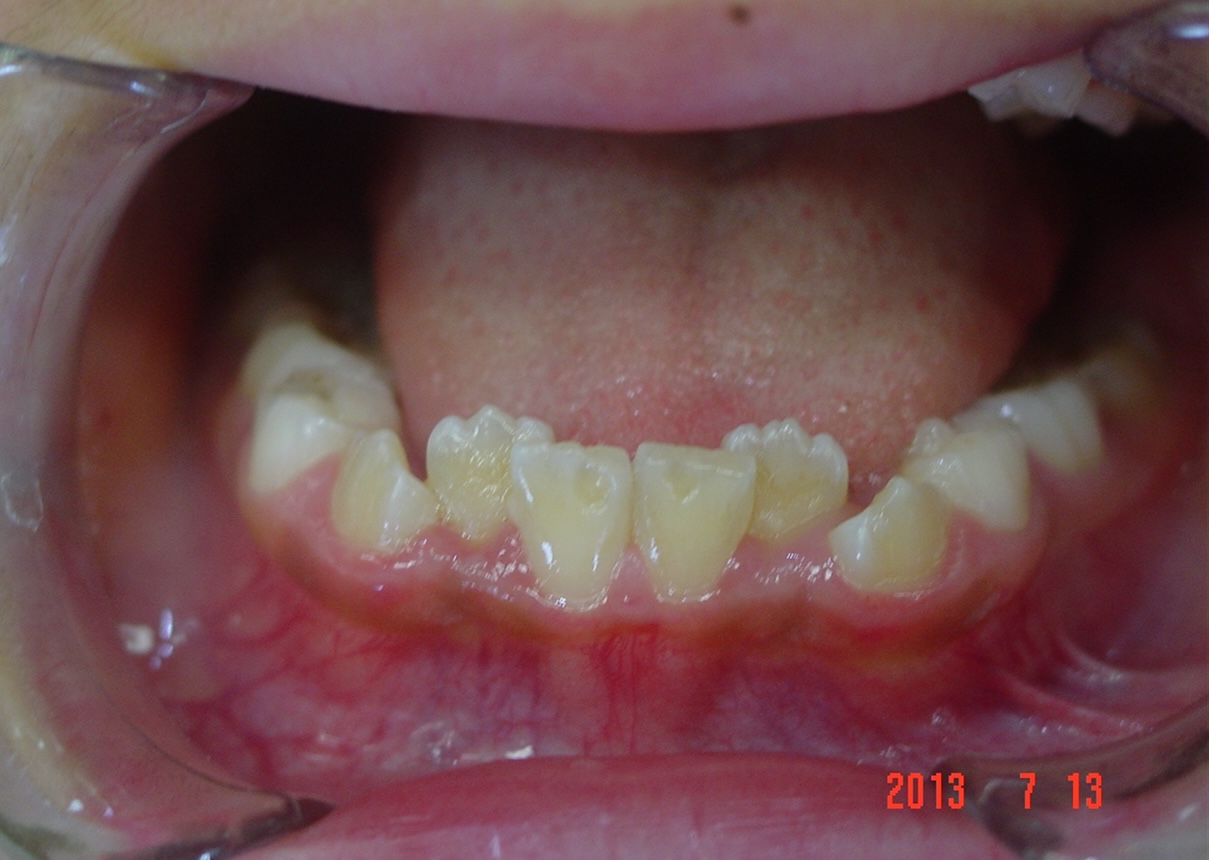

矯正前

| 症状 | 左上2番3番逆転症例 |